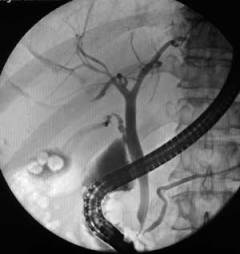

-

Ретроградная холангиопанкреатография – рентгенография желчного пузыря и желчевыводящих путей, которая выполняется после введения в них контрастного вещества через зонд.